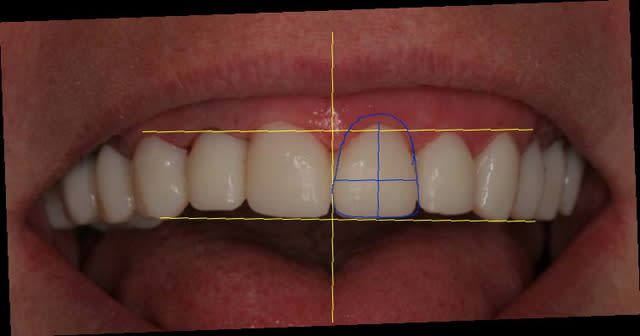

Pour tes centrales, elles sont un peu courtes.

Voir dessin fait rapido.

Les collet sont trop horizontaux.

Pour la centrale et la canine, ils devraintt être plus haut que la lattérale.

Une centrales doit faire entre 10 et 12 mm en hauteur, avec un rapport largeur sur longeur de 75-80 %

La 11 est aussi plus carrée que la 21